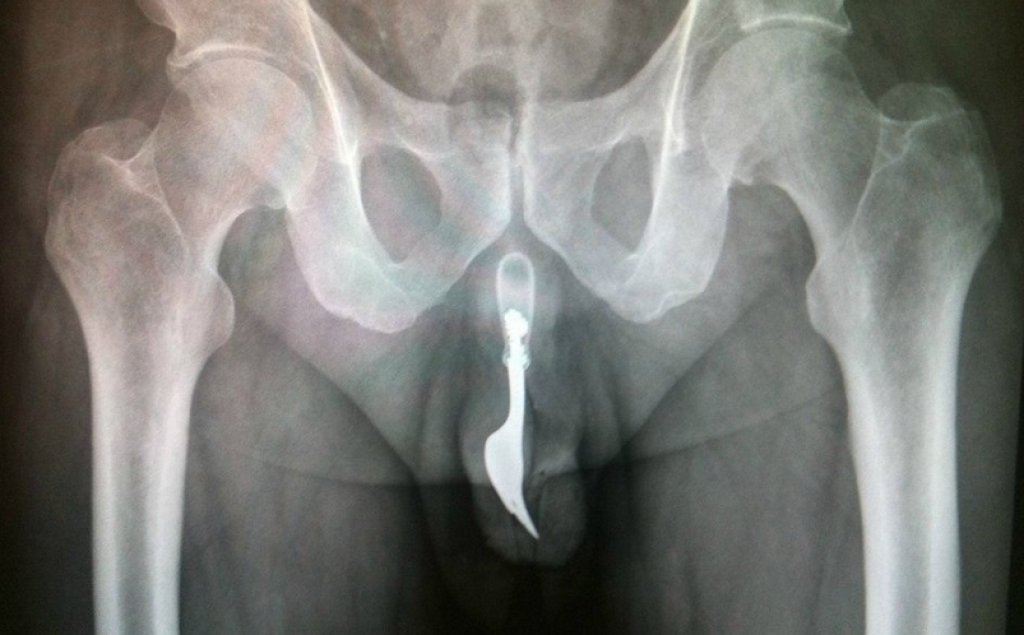

Е, той не може, но тези снимки говорят сами за себе си. И за хората, чиито са. Хора с (меко казано) доста извратени сексуални фантазии.

Тези осем примера показват това, което рентгенът не може да каже и затова докторите го правят вместо него. Вижте ги в галерията.